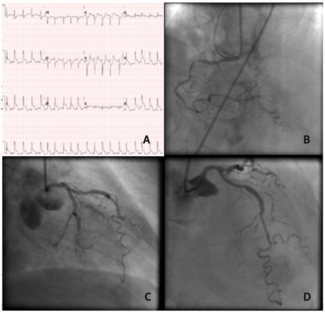

A 66-year-old male presented with ST–segment-elevation myocardial infarction. Emergent coronary angiography showed thrombotic occlusion of the distal right coronary artery (RCA). Percutaneous coronary intervention (PCI) of the culprit RCA...